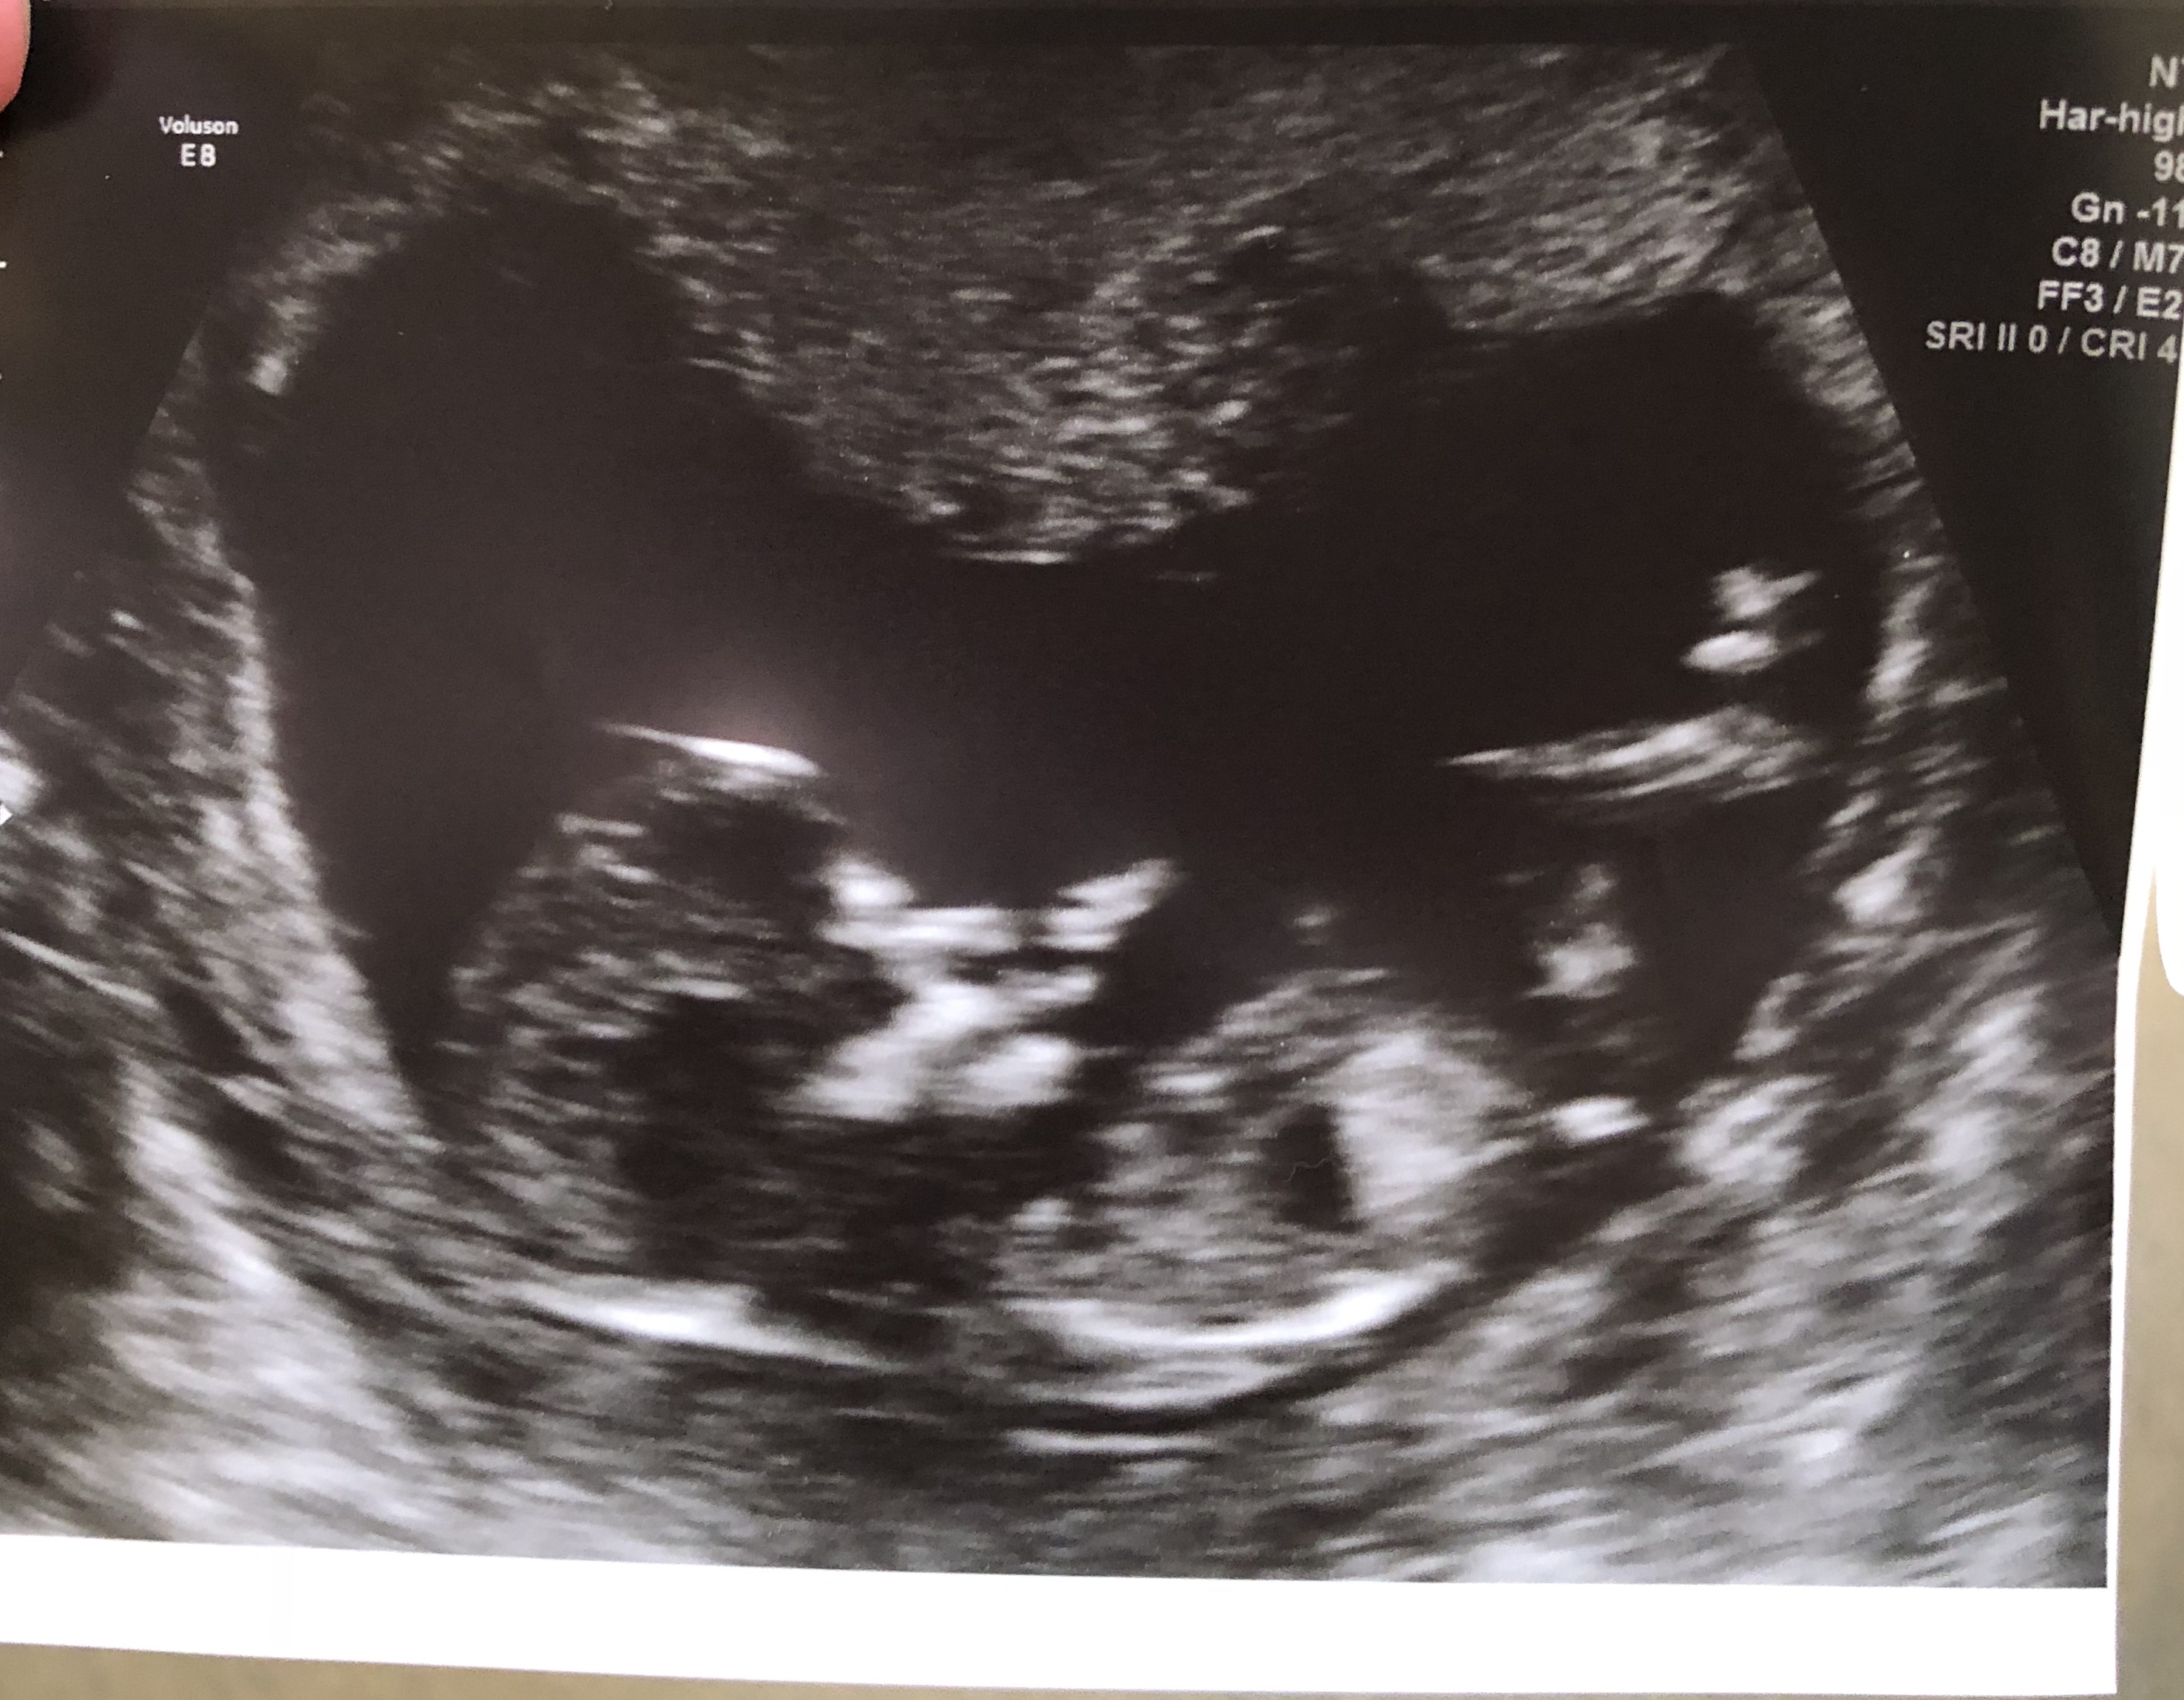

Hi! So the tech said she thinks this baby is a girl but obviously it’s still early! Any guesses? The nub on the live ultrasound was super long and forked, not sure if that matters at all! I have been hoping for a boy but will be happy with either. Thank you